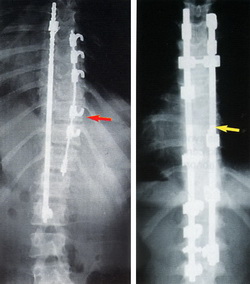

There is actually more than one scoliosis surgery procedure, but the results of these will be similar. The first procedure involves opening up an incision in the patient's back and inserting rods and wires to fuse the spine into alignment. This is not a simple procedure and it can take a long time to perform; it may be as long as six hours in theatre. The other scoliosis surgery procedure involves going in from the front; the surgical team will need to deflate a lung to get to the spine. Following this treatment the movement of the patient will need to be restricted for about seven months. If the scoliosis surgery procedure is being performed on young children then it may be decided to use growing rods; these rods will be adjustable as the child grows and this can be done without the need for further surgery.